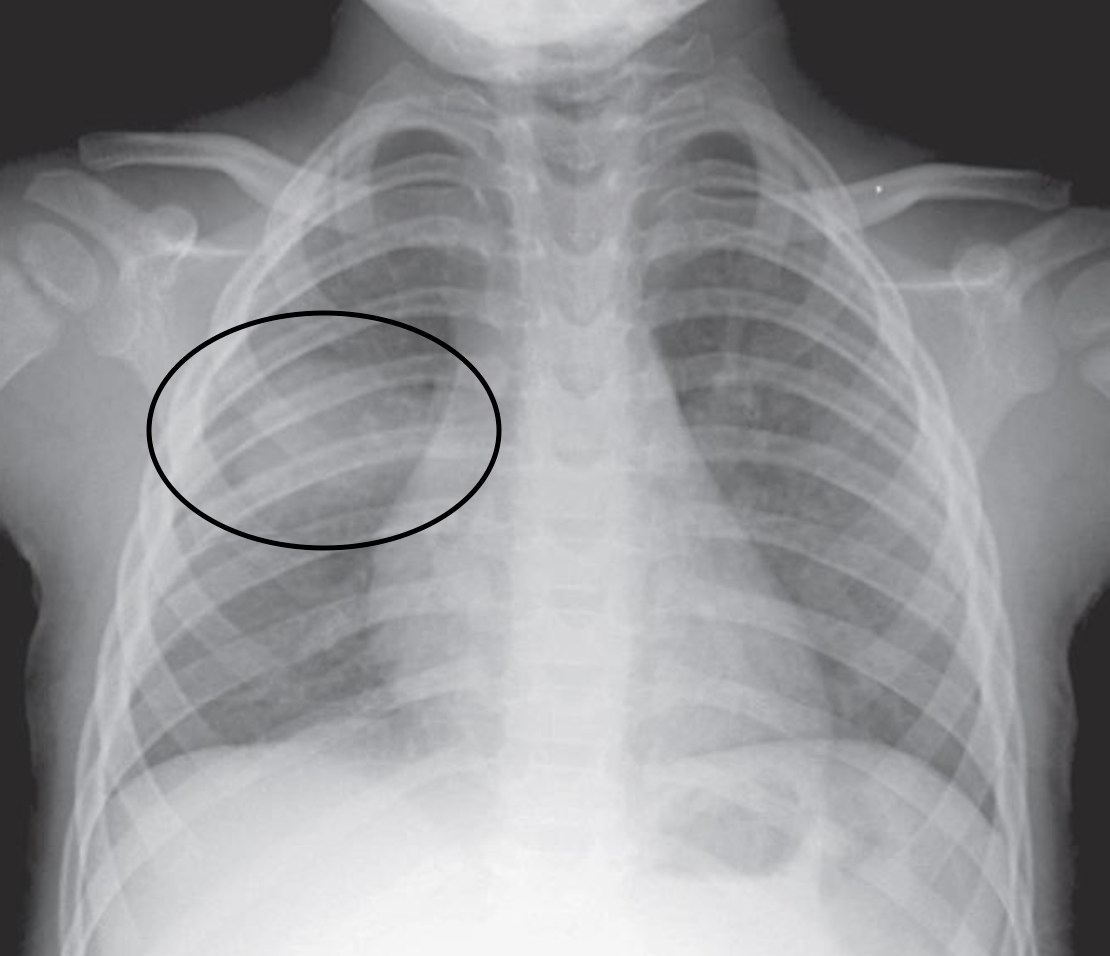

Снимок грудной клетки здорового ребенка: примеры и диагностика